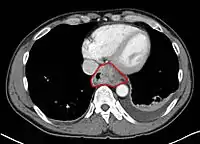

• Middle thoracic esophagus:

• Lower border of the azygos vein to the inferior pulmonary veins

• By endoscopy, 25 to <30 cm